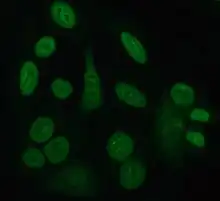

Indirect immunofluorescence is one of the most commonly used tests for ANAs. Typically, HEp-2 cells are used as a substrate to detect the antibodies in human serum. Microscope slides are coated with HEp-2 cells and the serum is incubated with the cells. If the said and targeted antibodies are present then they will bind to the antigens on the cells; in the case of ANAs, the antibodies will bind to the nucleus. These can be visualised by adding a fluorescent tagged (usually FITC or rhodopsin B) anti-human antibody that binds to the antibodies. The molecule will fluoresce when a specific wavelength of light shines on it, which can be seen under the microscope. Depending on the antibody present in the human serum and the localisation of the antigen in the cell, distinct patterns of fluorescence will be seen on the HEp-2 cells.[51][52] Levels of antibodies are analysed by performing dilutions on blood serum. An ANA test is considered positive if fluorescence is seen at a titre of 1:40/1:80. Higher titres are more clinically significant as low positives (≤1:160) are found in up to 20% of healthy individuals, especially the elderly. Only around 5% of the healthy population have ANA titres of 1:160 or higher.[8][53]

There are many nuclear staining patterns seen on HEp-2 cells: homogeneous, speckled, nucleolar, nuclear membranous, centromeric, nuclear dot and pleomorphic. The homogeneous pattern is seen when the condensed chromosomes and interphase chromatin stain. This pattern is associated with anti-dsDNA antibodies, antibodies to nucleosomal components, and anti-histone antibodies. There are two speckled patterns: fine and coarse. The fine speckled pattern has fine nuclear staining with unstained metaphase chromatin, which is associated with anti-Ro and anti-La antibodies. The coarse staining pattern has coarse granular nuclear staining, caused by anti-U1-RNP and anti-Sm antibodies. The nucleolar staining pattern is associated with many antibodies including anti-Scl-70, anti-PM-Scl, anti-fibrillarin and anti-Th/To. Nuclear membrane staining appears as a fluorescent ring around the cell nucleus and are produced by anti-gp210 and anti-p62 antibodies. The centromere pattern shows multiple nuclear dots in interphase and mitotic cells, corresponding to the number of chromosomes in the cell. Nuclear dot patterns show between 13 and 25 nuclear dots in interphase cells and are produced by anti-sp100 antibodies. Pleomorphic pattern is caused by antibodies to the proliferating cell nuclear antigen.[26][53][57][58] Indirect immunofluorescence has been shown to be slightly superior compared to ELISA in detection of ANA from HEp-2 cells.[54]